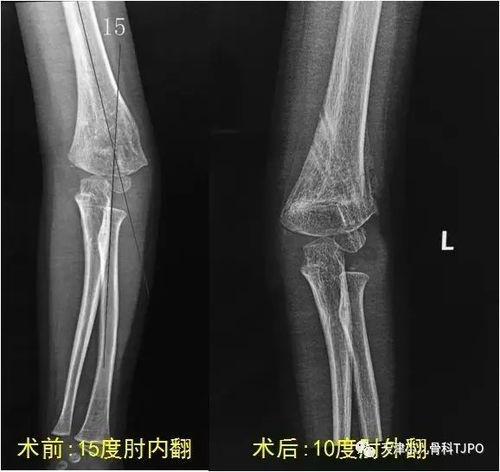

4. 检查复位效果:复位后,再次观察肘关节,确认是否已经恢复到正常位置。